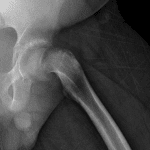

Age: 12

Sex: Male

Indication: Left hip pain

- Abnormal widening and lucency of the left proximal femoral physis

- Left hip is located

- Slipped capital femoral epiphysis (SCFE)

Abnormal widening and lucency of the left proximal femoral physis, concerning for slipped capital femoral epiphysis (SCFE). Recommend frog-leg lateral view of the hips for further evaluation.

Left hip is located.